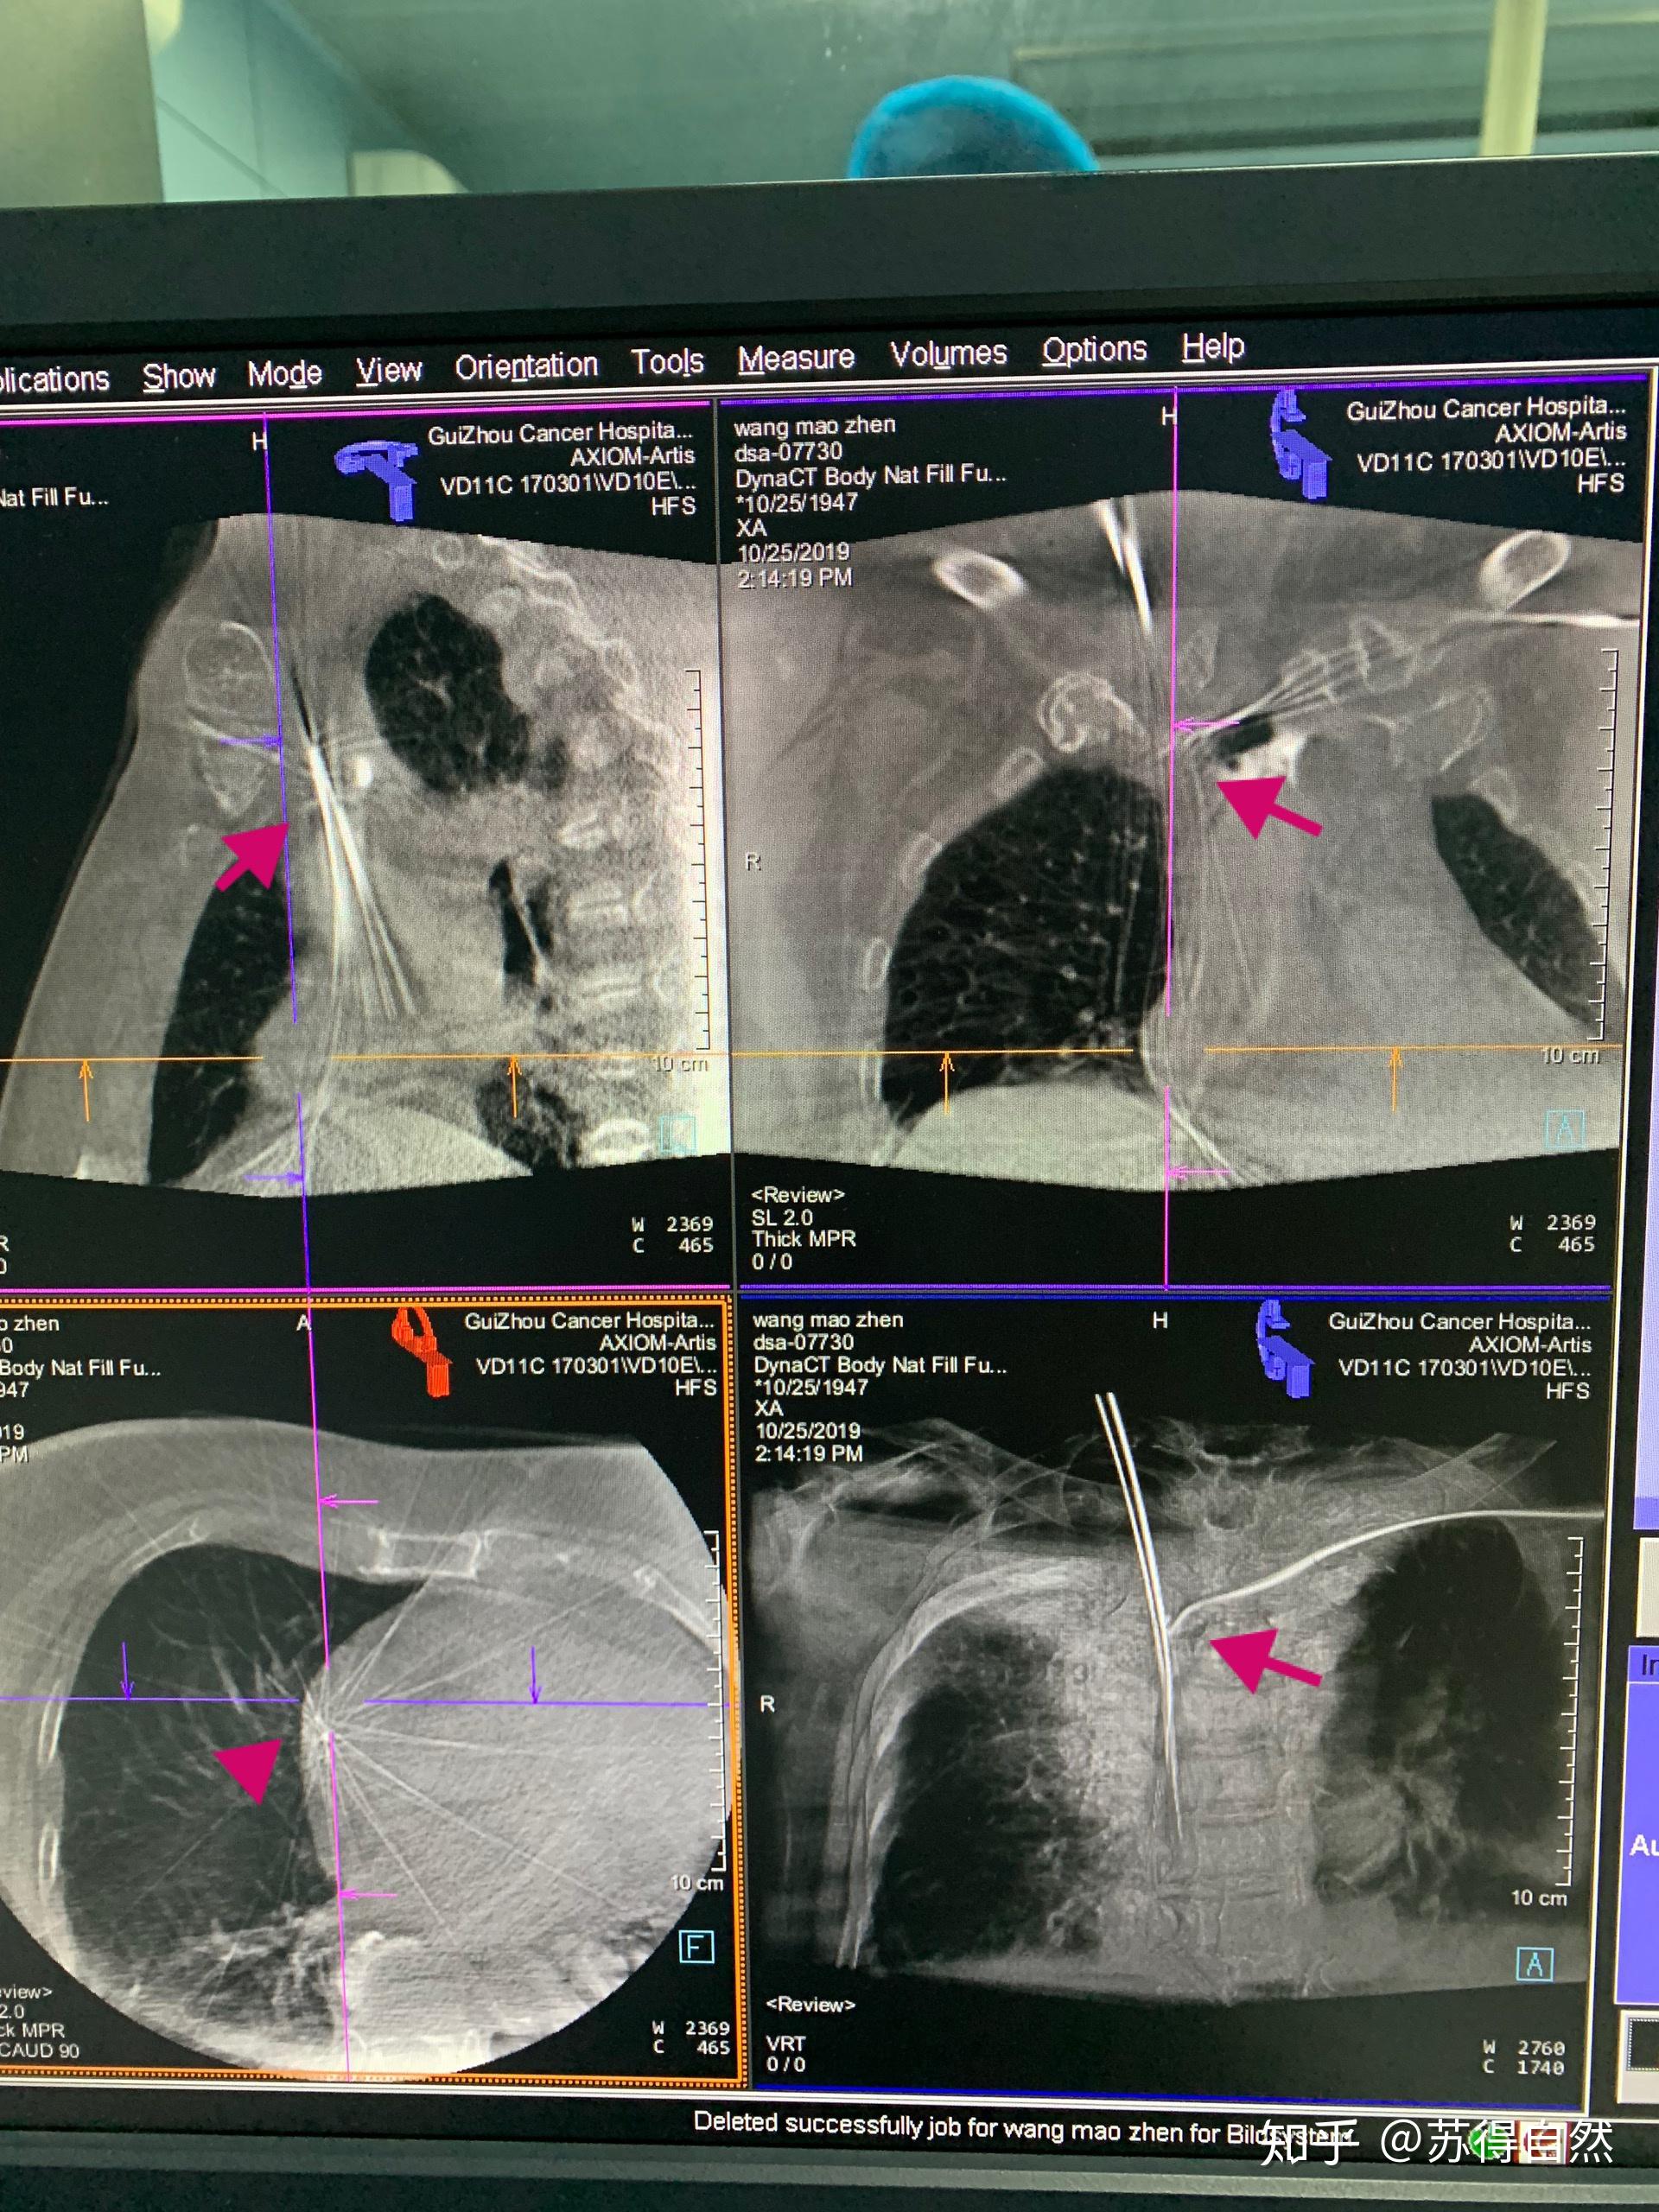

直穿上腔静脉开通左侧头臂静脉 - 知乎